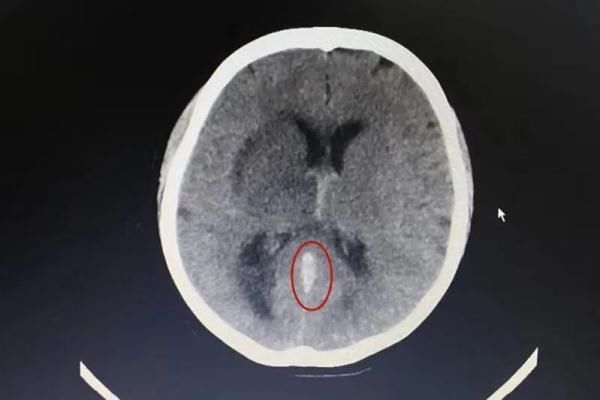

第三天,家人将其转入南方医科大学珠江医院神经内科。“患者来的时候,检查结果显示已经有脑积水的迹象,病情非常紧急了”,接诊的医生表示。详细询问病史得知,王女士因有“子宫腺肌病”,规律地吃了1年“避孕药”,医生高度怀疑王女士有颅内静脉血栓,立即完善急诊头颅CT及头颅MRV+颅脑MR增强扫描检查,果不其然,王女士大脑大静脉、大脑内静脉和直窦都有血栓,双侧丘脑、基底节区、胼胝体膝部及透明隔静脉阻塞性脑梗死。

医生解释,大脑大静脉是连接和汇入直窦的最大脑静脉,大脑大静脉与直窦主要引流大脑深部的静脉血流,而大脑内静脉是大脑半球深部静脉的主干。这几个关键位置出现血栓,若不及时诊断和处理,会危及生命。